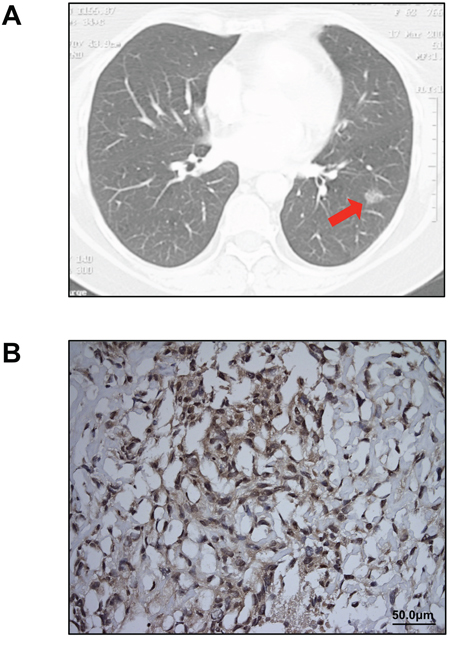

A 62-year-old Caucasian woman presented with persistent symptoms of fever, cough, chest pain and a left lower lobe consolidation on chest radiograph despite the use of antibiotics. Six months later, computed tomography of the chest revealed a discrete mass in the left lower lobe, which fine needle aspiration showed to be non-small cell lung cancer (Figure 1A). Positron emission tomography and a bone scan revealed no evidence of distant metastasis, and the patient was referred for a thoracic surgery evaluation. Her past medical history was significant for bladder cancer treated with transurethral bladder resection eight years earlier. She was a former smoker with a 30 pack-year history and had worked for a construction company while in her forties with possible, but uncertain asbestos exposure.

Figure 1: Clinical diagnosis of lung adenocarcinoma and MPM. A. A 2 cm ground-glass opacity (arrow), later diagnosed as lung adenocarcinoma, was identified in the patient’s left lower lobe on chest CT scan. No pleural thickening or implants were noted on preoperative imaging. B. Immunohistochemical staining for calretinin confirmed the diagnosis of MPM (original magnification 20X).

Five months after her initial presentation, the patient underwent a left lower lobectomy with mediastinal lymph node dissection. On thoracotomy, scattered mass lesions were incidentally discovered on the pleural surface of the diaphragm and biopsied. Final pathology revealed a T1N0M0 lung adenocarcinoma in the left lower lobe and pleural biopsies indicated sarcomatoid pleural mesothelioma, which stained positive for calretinin (Figure 1B) and was staged as T3N0M0 because there was no evidence of venous, arterial, lymphovascular, or perineural invasion. Postoperatively, two cycles of neoadjuvant chemotherapy with carboplatin and pemetrexed resulted in some disease regression. The patient had a subsequent completion left pneumonectomy. She died from mesothelioma progression four months later.